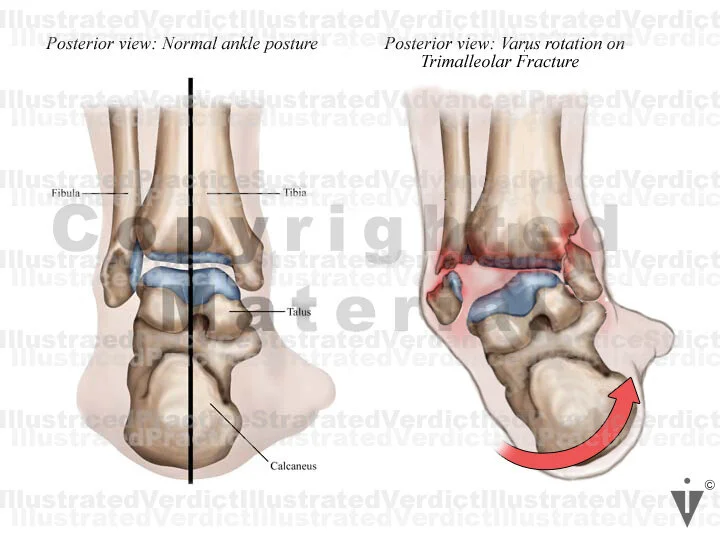

BOARD 7

1. Normal posterior ankle: Bony structures

2. Varus rotation on trimalleolar fracture